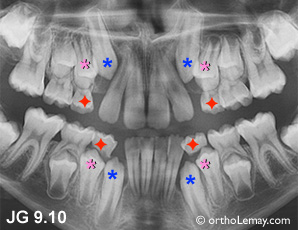

Cas GQ-JG

Cas GQ : Problèmes d’éruption et manque d’espace. Les incisives latérales de chaque arcade sont larges et n’auront pas l’espace suffisant pour faire éruption convenablement. Il y a de fortes chances qu’elles sortent du côté de la langue. Il serait indiqué d’extraire les canines temporaires (rouge).

Cas JG : Après la sortie des latérales, ce sont les canines et premières prémolaires qui sont les prochaines dents à tenter de faire éruption mais qui manquent sévèrement d’espace. L’extraction des premières molaires temporaires (rouge) accélérera l’éruption des prémolaires et, à l’arcade du haut, peut aider à rediriger l’éruption des canines qui se dirigent sur les latérales. (Voir la légende pour identifier les dents)